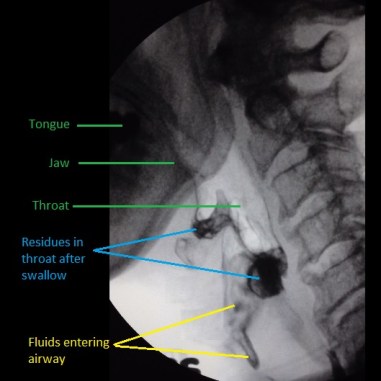

VFS (also known as modified barium swallow) is a moving x-ray examination of swallowing. During the examination, patient will be asked to chew and/or swallow food/liquids of different texture or consistencies. The videos obtained will allow detailed analysis of the swallowing functions for better treatment and management planning.